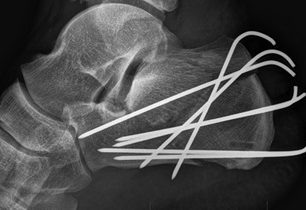

Ještě ten den večer jdu na sál. Zlaté ruce Fildy za hodinu spletli na mé patě ze sedmi drátů klec, něco jako když se o Velikonocích splétá pomlázka a uvěznili v něm ježka. Respektive myšlenku mi vnukl až pohled přes rameno na rentgenový snímek s daným výtvorem a samolibě spokojeného umělce. Celý akt té řezničiny byl zakončen hlubokým hlasem Alfa samce s rouškou na tváři, v podobě pochvalné ódy na sebe sama a slovy, „Fakt se mi to povedlo.“